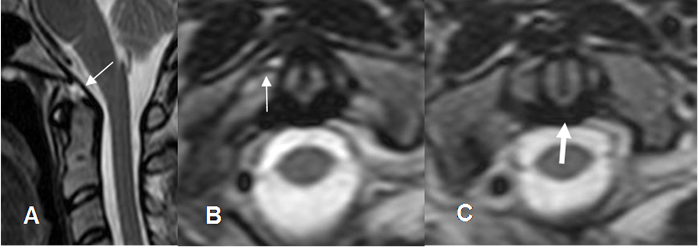

Hay múltiples ligamentos en la unión cráneo espinal, pero solo 3 son considerados los principales estabilizadores. (6, 8). (Fig 4).

Fig 4. Ligamentos de unión craneoespinal.

A: RM sagital en T2. Membrana tectorial.

B y C: RM axial en T2. Ligamento alar (Flecha delgada) y ligamento transverso (Flecha gruesa).